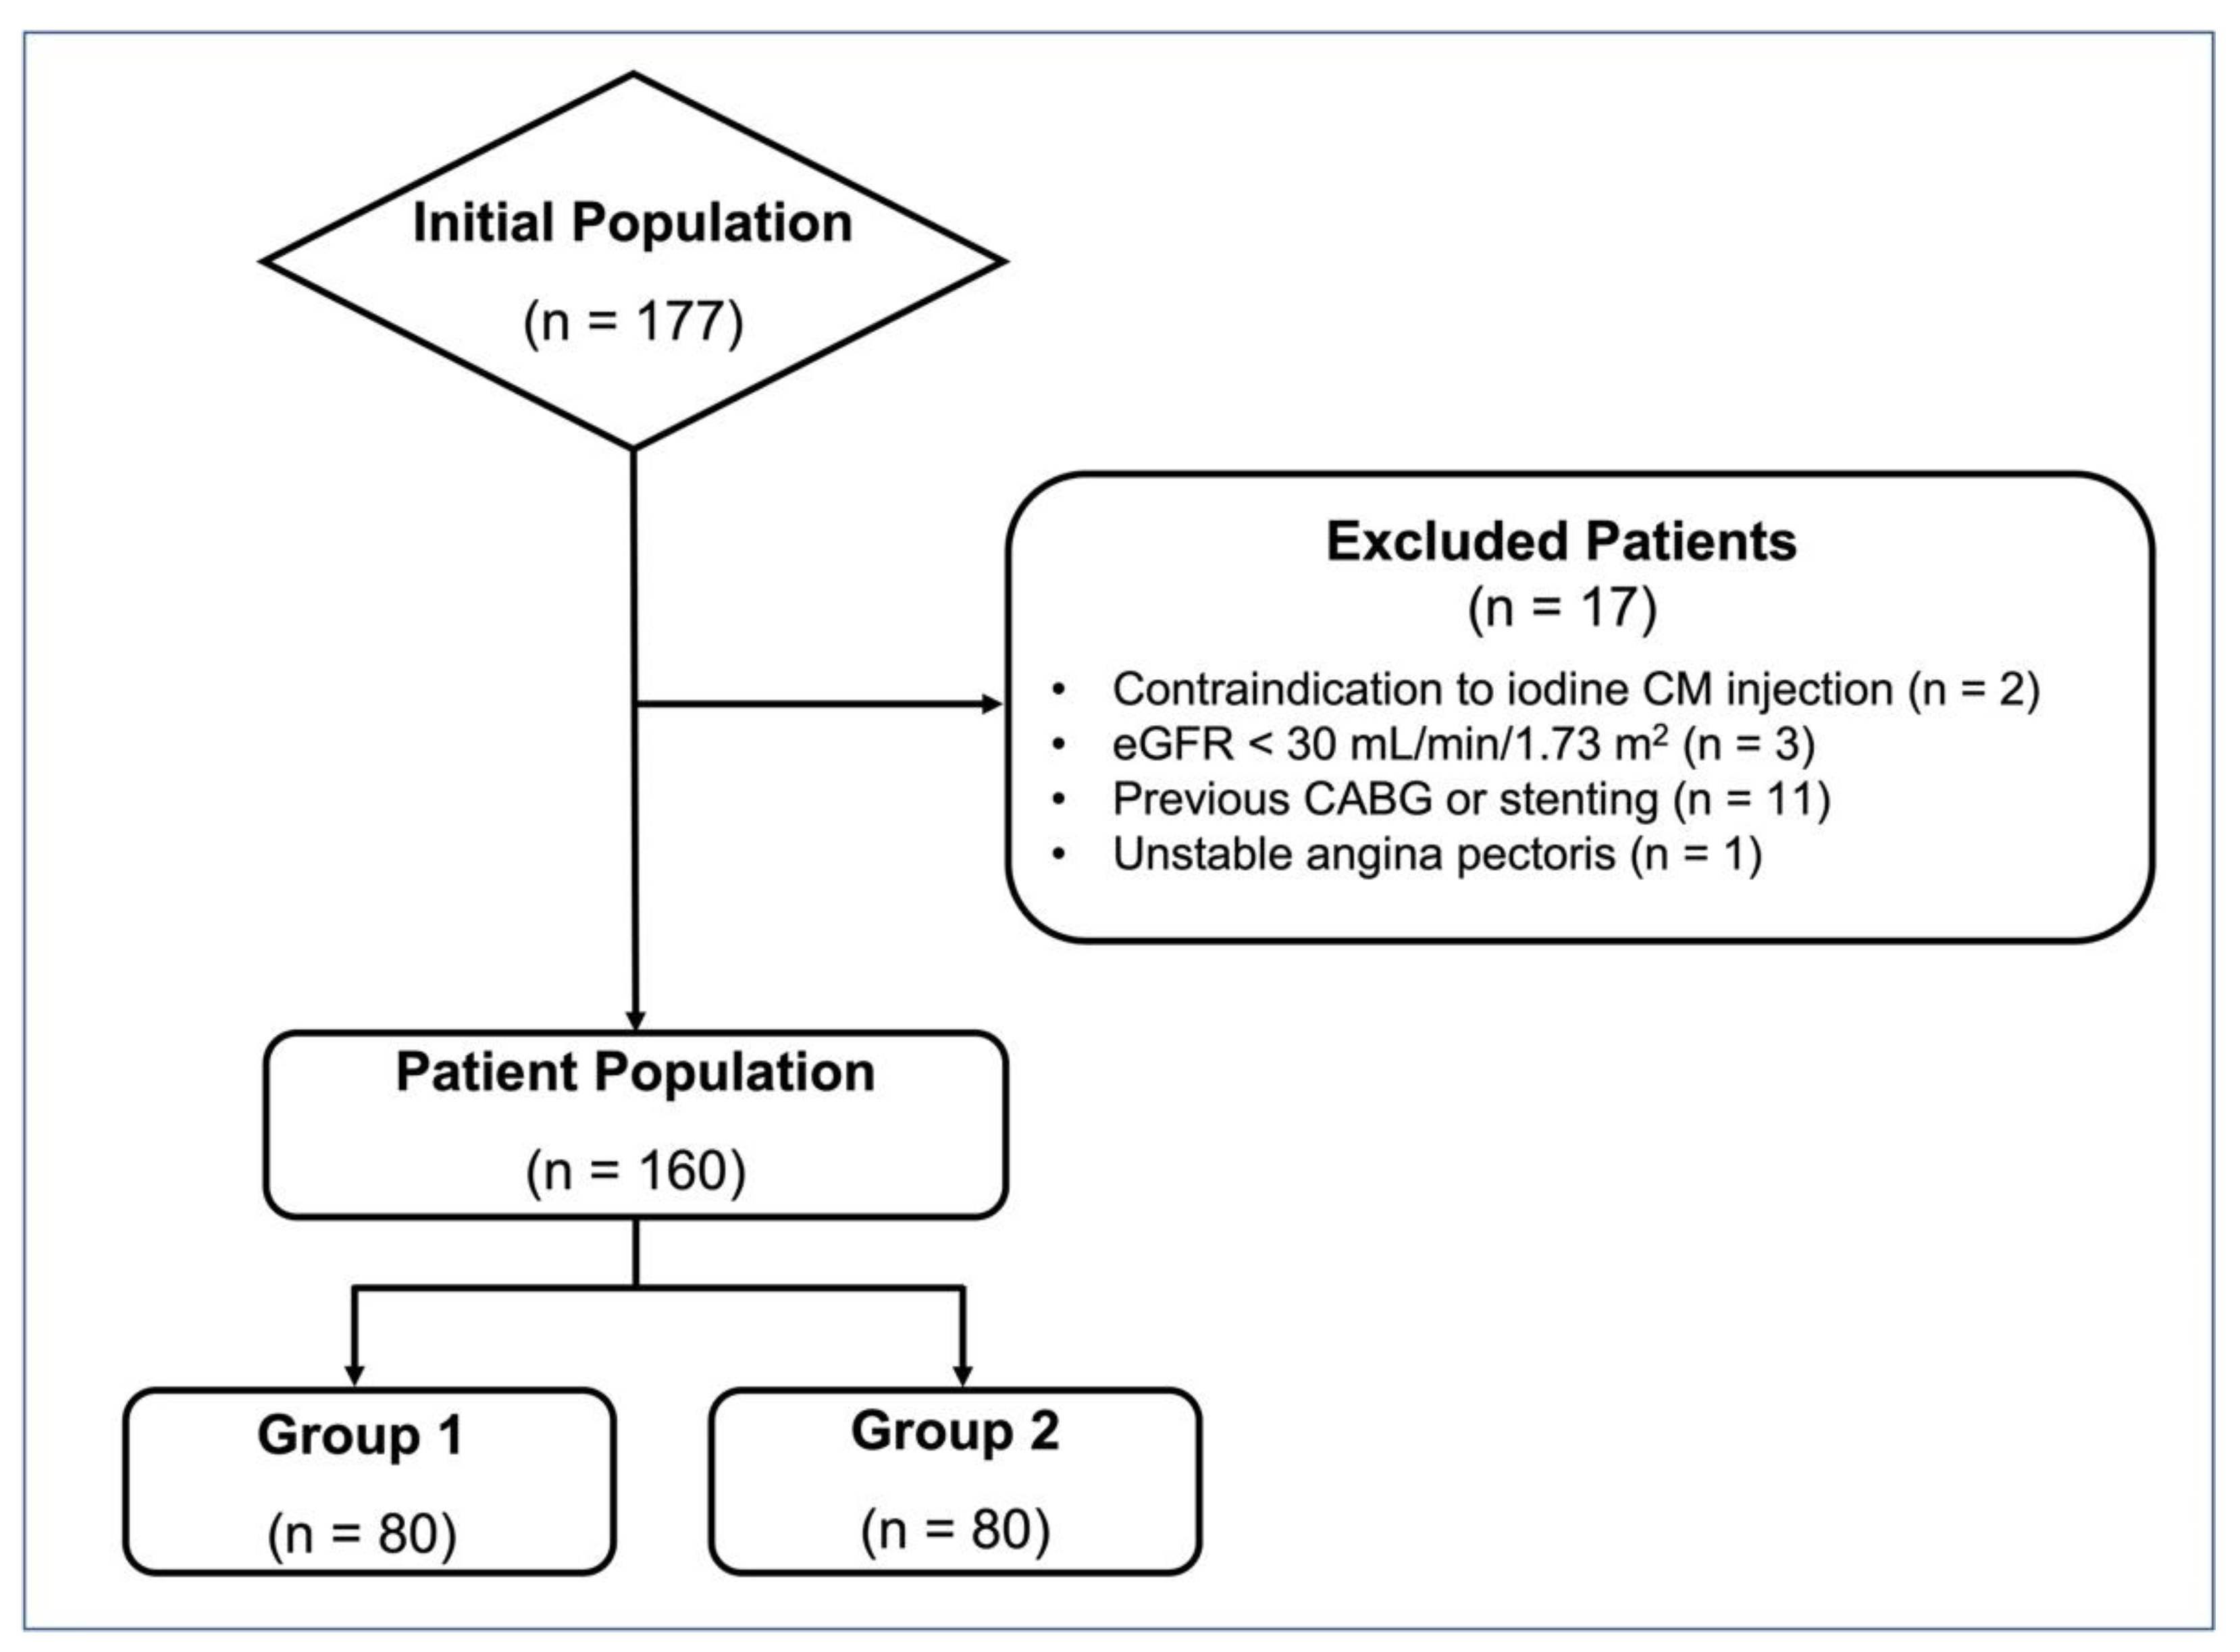

2.1. Patient Population

3.1. Patient Population